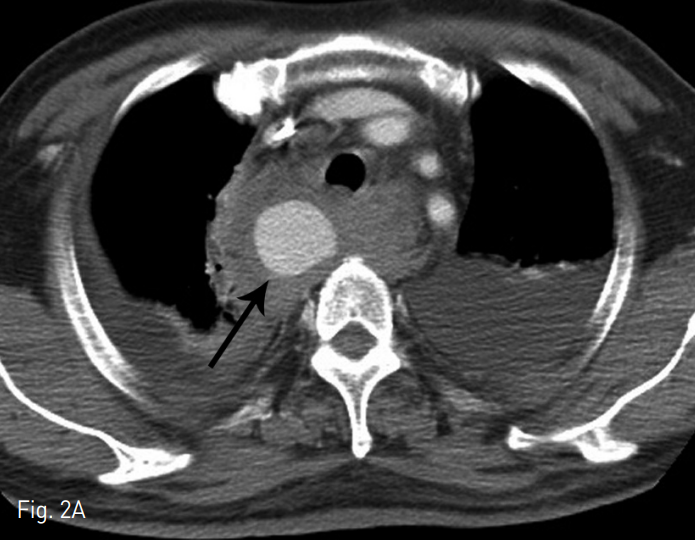

단순 X-ray촬영상 기관지 우측으로 확장된 음영이 관찰되었고 (Fig. 1) CT 검사상 우측 척추동맥에서 발생된 큰 가성동맥류가 관찰되고 (Fig. 2) 우측 종격동내에는 다량의 혈종이 보였다.

Fig. 2

Axial (A) and multiplanar reformatted (B) images showing large pseudoaneurysm (black arrows) at the right side supramediastinum with surrounding hematoma. The pseudoaneurysm is originated from proximal right vertebral artery (VA, white arrow)